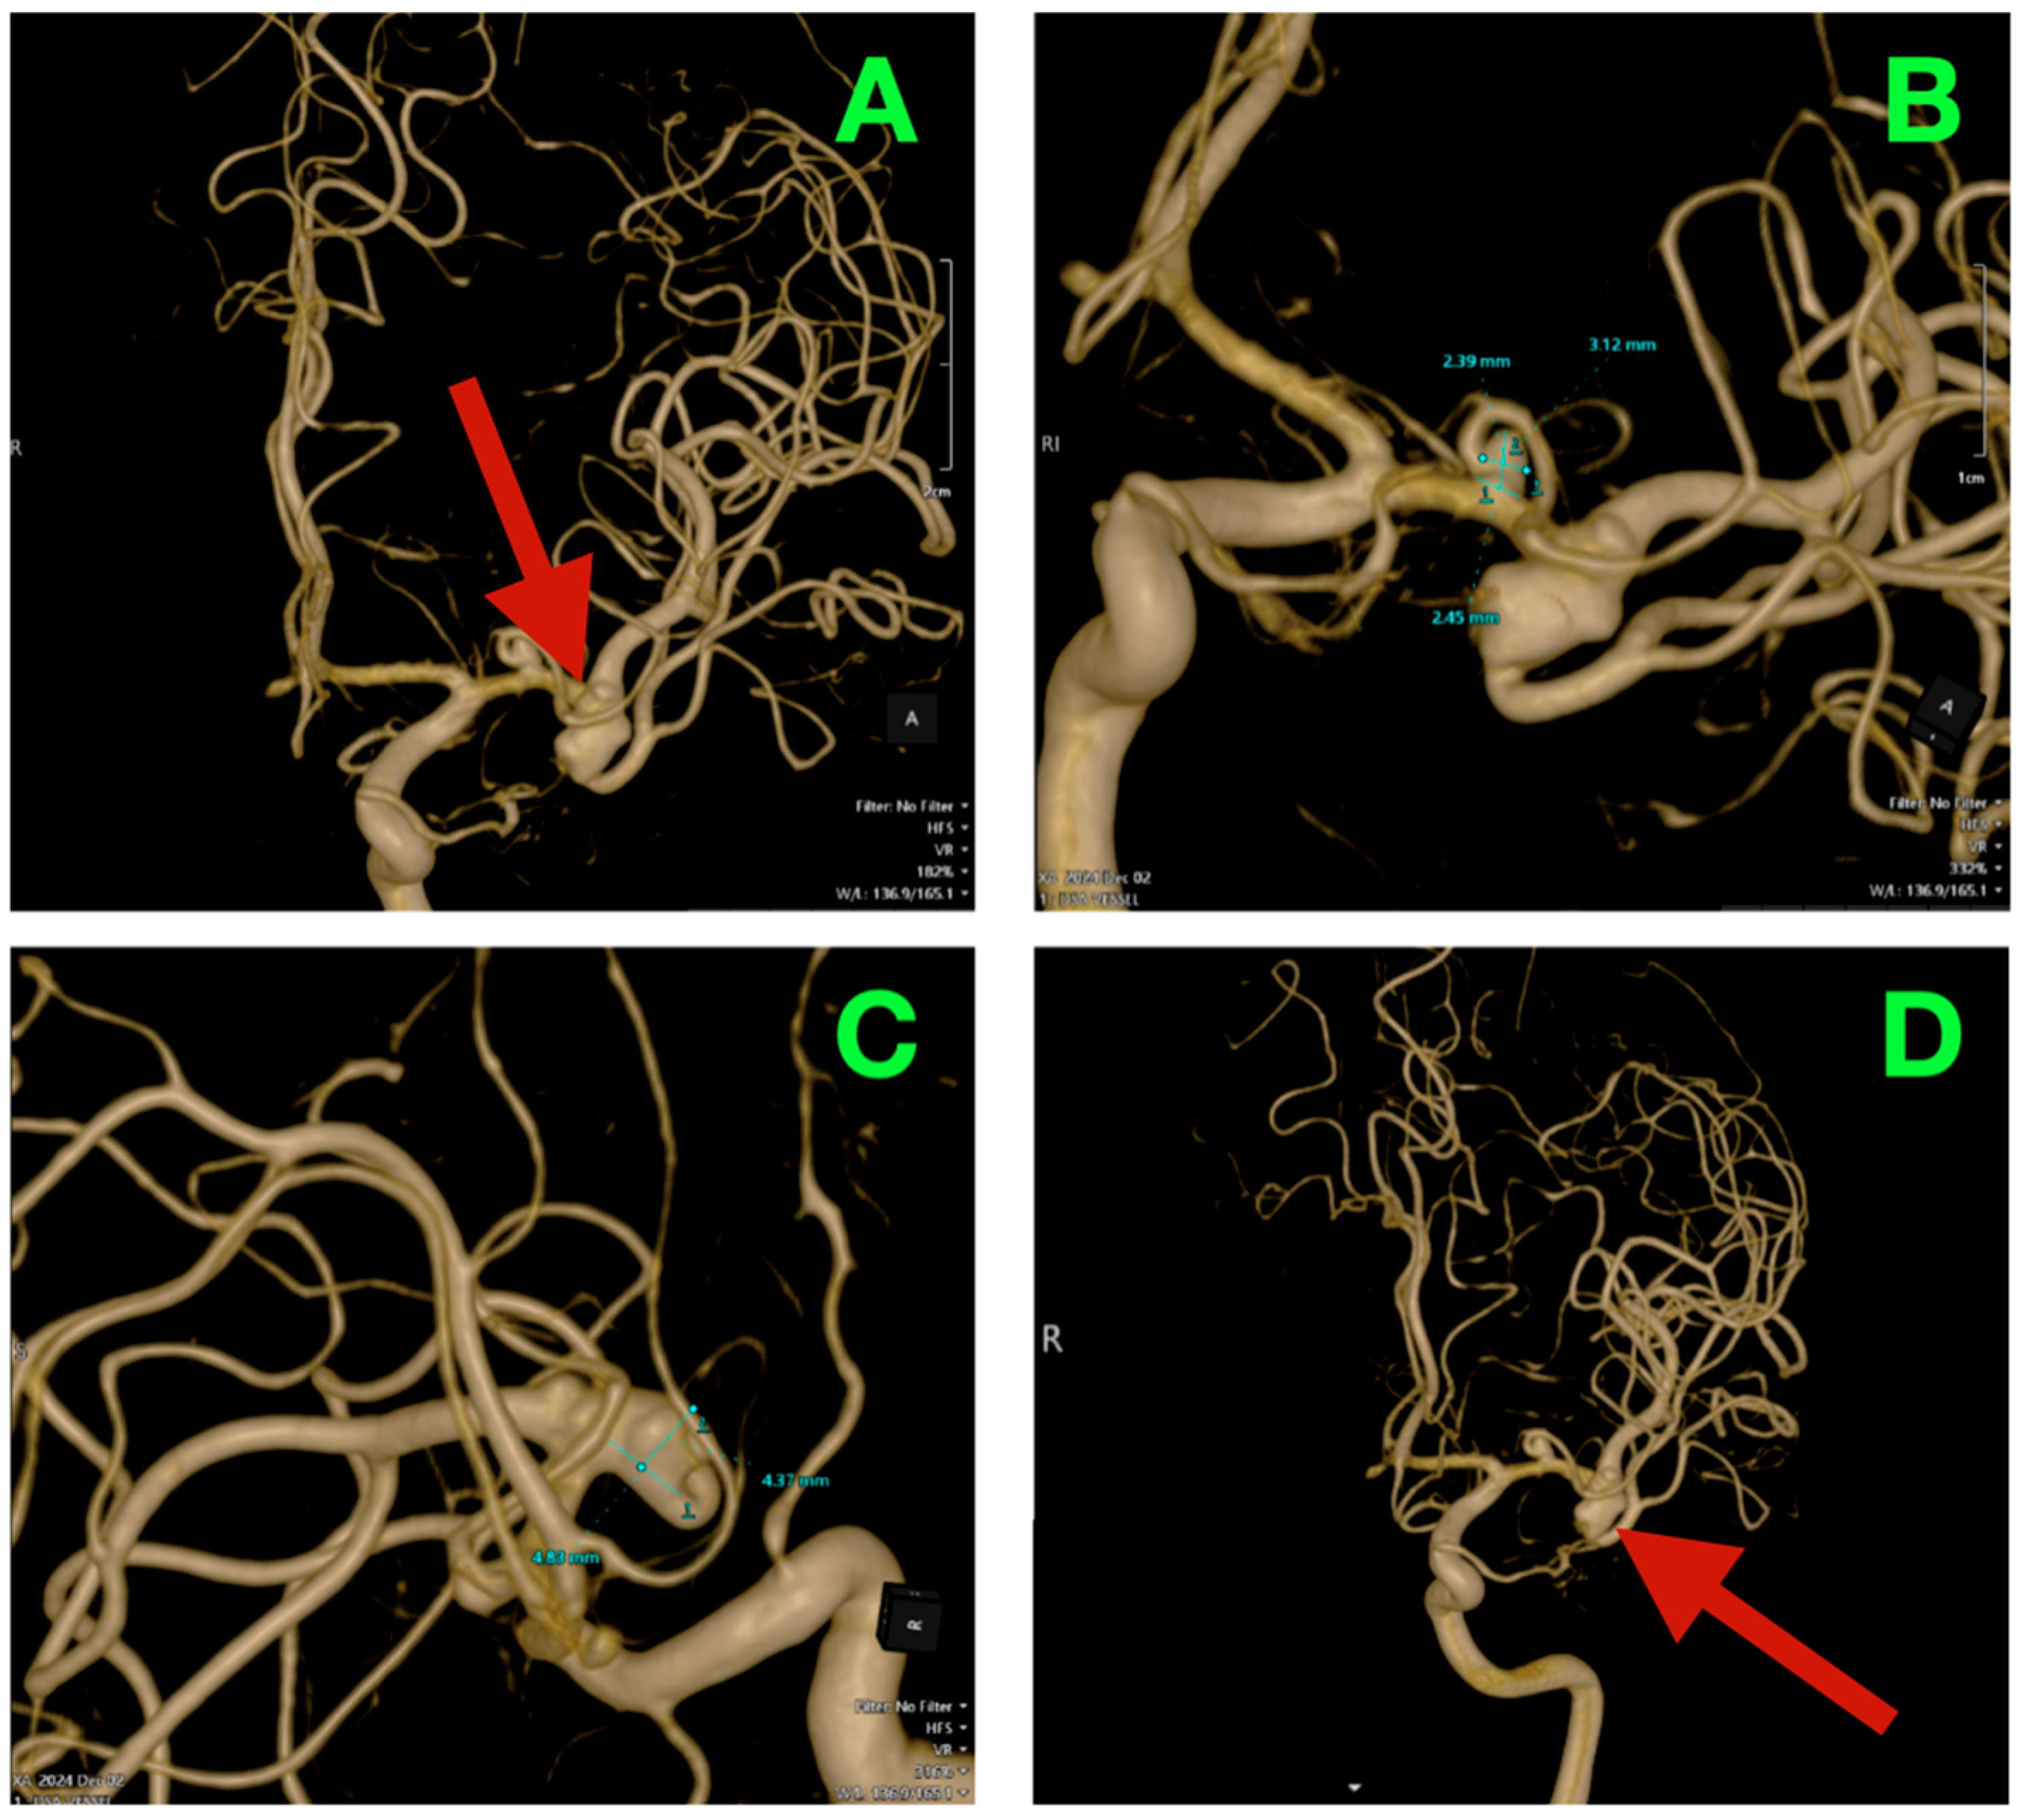

High-resolution 3D rotational angiographic volumes were collected, and volumetric rendering and CTA were undertaken (Figure 2A–D). This reconstruction optimally adapted to isolate the traditional overlap of vessels or planar angiography and enabled surgical simulation. Additionally, it offered analysis of neck geometry, dome orientation, and angles of take-off of the branches in orthogonal planes, along with great detail to preoperative planning, discarding a virtual “clip trajectory” workable area. The anterosuperior projection of the bifurcation aneurysm was again confirmed, with the dome axis pointing toward the mid-insular cortex. The superior M2 trunk had a narrow angle of take-off at 54° from the superior neck border, while the inferior trunk originated in a more posterior and inferior orientation with a 68° angle that created an acute “tight fork”. This neck geometry significantly reduced tolerance for misalignment of the clip blade because even slight decreases in alignment can add a partial increase in compromise of the lumen—especially if the clip was aligned in a position that would yield a submillimeter misalignment. The neck contained 1.8 mm of orifice from the superior M2 and 1.4 mm of orifice from the inferior M2, as calculated on centerline flow reconstruction. The perforator anatomy of the M1 fusiform aneurysm was elaborated upon with remarkable fidelity. The lenticulostriate had explicitly dissipated perpendicularly on the dorsal wall with their immediate posterior vector direction of the perforated substance. The two biggest perforators measured 460 μm and 420 μm at their origins and were tapering quickly within 1.2 mm of take-off. This made both arteries very sensitive to even glass-like movement in the parent vessel from the clip applied to the bifurcation lesion. The inter-aneurysmal distance was short at 4.7 mm, which allowed for potential mechanical manipulation of the other vessel even if we only performed the dissection on one lesion.

Figure 2.

Three-dimensional rotational angiography and CTA volumetric reconstruction of the left MCA complex. (A) 3DRA, left internal carotid artery injection, anterolateral oblique projection. The bifurcation aneurysm arises at the M1 division point, with the broad neck partially incorporating both superior and inferior M2 origins. Note the anterosuperior dome projection toward the mid-insular cortex and the tight angular divergence of the M2 trunks (“tight fork” configuration), leaving minimal tolerance for clip blade malrotation. (B) 3DRA, orthogonal craniocaudal projection. The dome’s spatial relationship to the superficial Sylvian venous complex is evident, with the shortest opercular vein lying within 3 mm of the aneurysmal wall. The fusiform M1 dilation is visible proximally on the dorsal surface, directly within the lenticulostriate perforator belt. (C) CTA bone–vascular fusion, lateral projection. Depth mapping from the sphenoid ridge shows the bifurcation aneurysm positioned approximately 17 mm deep, corresponding to the mid-third Sylvian fissure corridor, while the fusiform aneurysm lies deeper (~23 mm), just proximal to the genu of the MCA. (D) CTA bone–vascular fusion, inferolateral projection. The lenticulostriate perforators arising from the fusiform M1 segment are visualized with submillimetric resolution, demonstrating perpendicular dorsal take-off toward the anterior perforated substance, underscoring the extreme vulnerability of these vessels to even minimal parent vessel displacement during bifurcation clip application.

Bone surface reconstruction suggested that the bifurcation aneurysm was situated approximately 17 mm deep to the sphenoid ridge, corresponding to the origin of the Sylvian fissure at or near the mid-third Sylvian fissure exposure, while the fusiform aneurysm was much deeper at 23 mm from this same cortical surface landmark, and just proximal to the genu of the MCA.